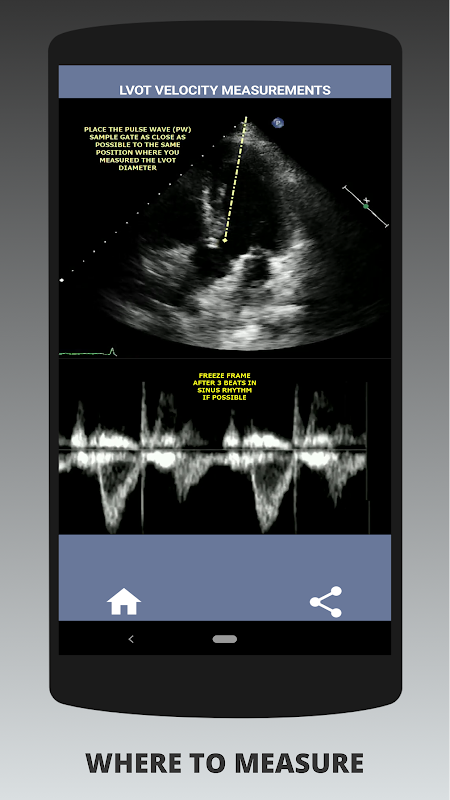

在我看来,如果面试者能够有力地展示这种技能,那么这个人比其他在这方面薄弱的申请人具有巨大的优势(这是合乎逻辑的,因为通常有很多主动脉瓣狭窄病例)。如果您正在申请心脏超声检查师职位、只需要更新技能的人或回声学生,那么此应用程序是由目前在职的心脏超声检查师为您设计的。简单而简短,直截了当,其中包含许多说明性视频,准确指出了测量的位置(例如 LVOT 直径)以及如何根据已发布的 ASE/ICAEL 指南进行测量。